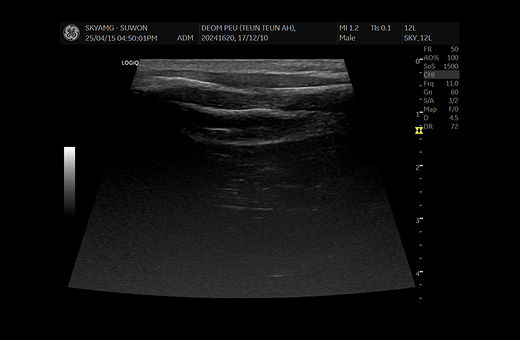

· 방사선 및 초음파 검사

대부분의 경우 배뇨 곤란으로 인해 병원으로 내원할 때는 방광이 매우 팽창 되어 있고, 내부의 슬러지가 많은 경우 내원하게 되며, 방사선 검사 및 초음파 검사를 통해 결석 유무 체크 방광 상태 및 슬러지의 분포 정도를 평가하게 됩니다.